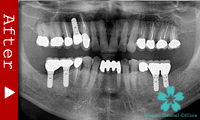

歯のない部分が広い場合

臼歯が失われた場合、従来は取り外し式の部分入れ歯で咬合機能を回復させてきました。

これに対し、インプラントなら天然歯と同様の感覚の”固定式”人工歯を入れることができます。